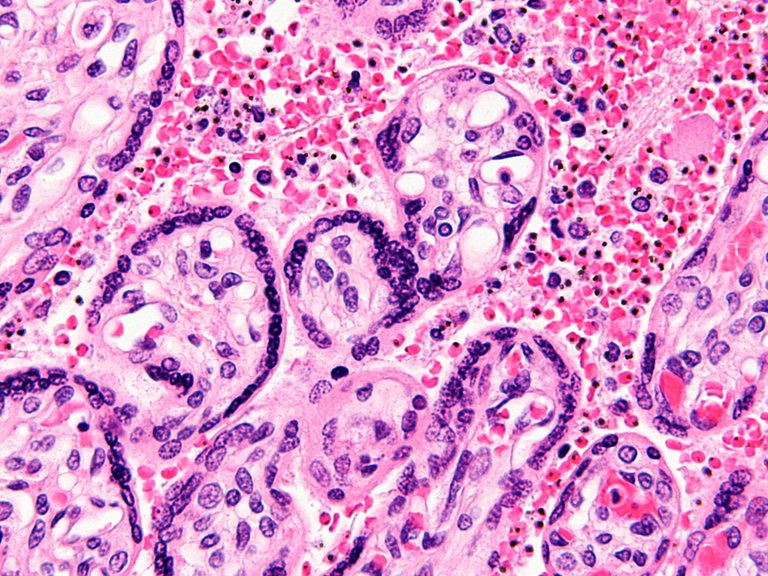

Ostalariaren globulu gorriak infektatu eta suntsitzen ditu malaria eragiten duen bizkarroiak, eta hemozoina deritzen kristalak kanporatzen ditu digestio-prozesuan. Malaria pigmentu izenez ezagutzen dira, eta itu interesgarria dira diagnostiko-teknika berriak garatu nahi dituzten ikertzaileentzat, bizkarroiaren barietate denek sortzen dituztelako, eta erregistro fosilean ere detektatu izan direlako (denboran aldatu gabe iraun duen prozesu metabolikoa den seinale). Halaber, ezaugarri magnetiko eta optiko bereizgarriak dituzte, odoleko beste molekula batek berak ez dituenak, eta, ondorioz, haiek detektatzea aski da pertsona kutsatua dela jakiteko. Alabaina, metodologia honen bidez ezin da jakin zein bizkarroi barietatek kutsatu duen gaixoa, eta tratamendua ez da berdina barietate guztientzat.